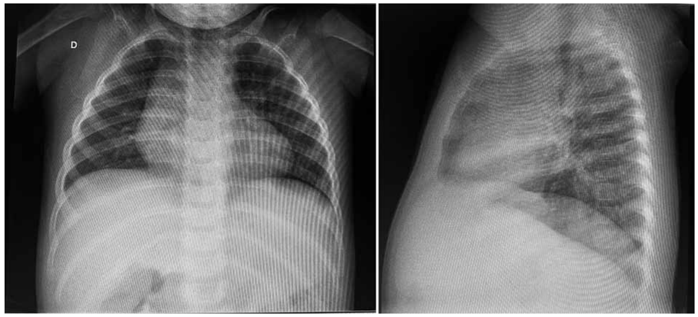

A figura a seguir apresenta a radiografia de tórax dessa paciente:

(Arquivo pessoal; imagem usada com autorização)